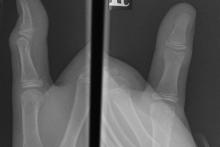

11-letni pacjent po urazie palca I-go ręki prawej

Przypadek 24: 11-letni pacjent po urazie palca I-go ręki prawej.

Rozpoznanie: W badaniu RTG stwierdzono złamanie przynasady bliższej paliczka dystalnego - ugięcie warstwy korowej od strony grzbietowej (strzałka).